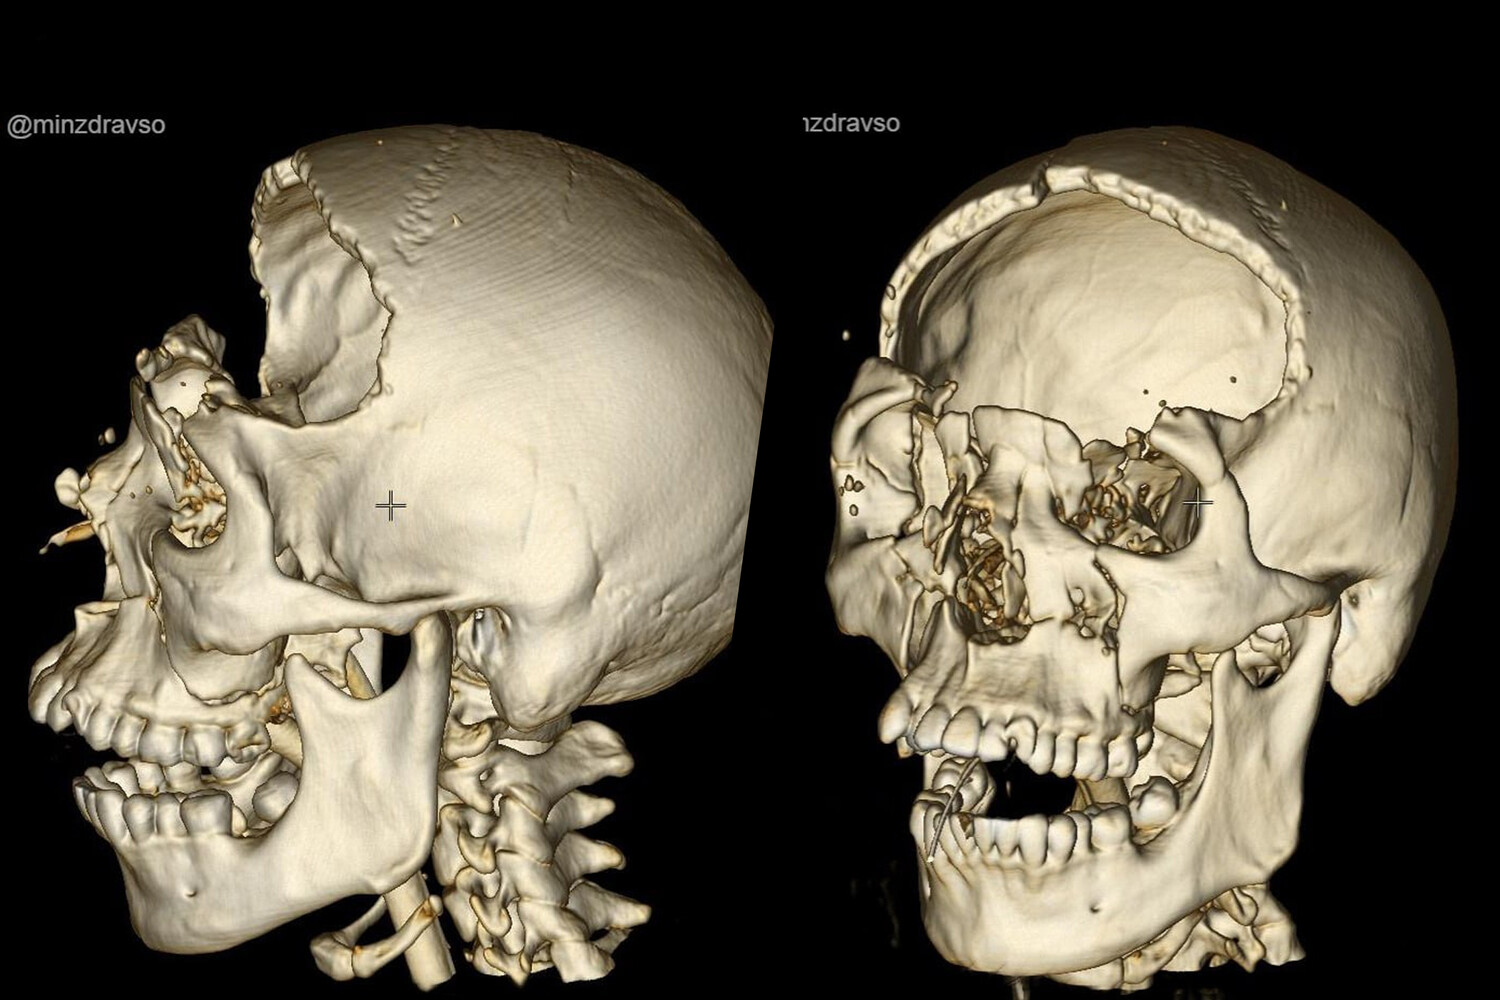

Молодой человек поступил в учреждение после аварии с раздробленным черепом и сразу был направлен на экстренную операцию.

Во время 2,5-часового вмешательства нейрохирурги провели бифронтальную трепанацию, остановили кровотечение, удалили гематому объемом 50 миллилитров, сделали пластику мозговой оболочки. По информации ведомства, благодаря слаженным и своевременным действиям специалистов удалось избежать тяжелых неврологических осложнений.